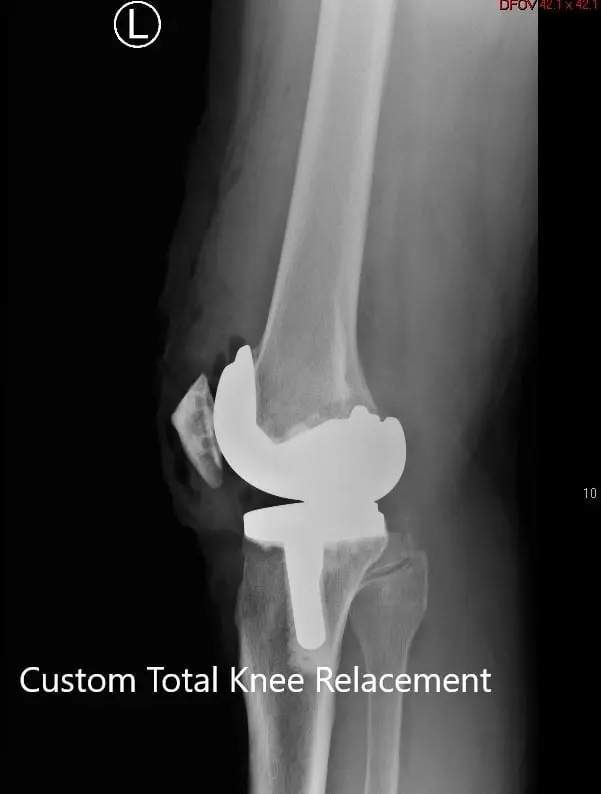

Postoperative X-ray showing the lateral views of both knees

Postoperative X-ray showing the lateral views of both knees - img 2

Postoperative X-ray showing the lateral views of both knees.

Postoperative X-ray showing the AP view of both knees

Postoperative X-ray showing the AP view of both knees.